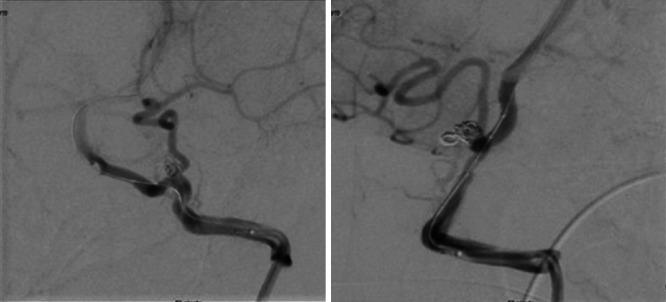

A 9-year-old male presented with altered mental status and seizures. Computed tomographic angiography showed aneurysmal SAH from a ruptured, left-sided posterior inferior cerebellar artery aneurysm. The patient underwent endovascular treatment with coiling and external ventricular drainage for SAH. Ophthalmological consultation for blurry vision revealed the diagnosis of Terson syndrome with decreased vision in the left eye, which was managed conservatively.

一名9岁男性出现精神状态改变和癫痫发作。计算机断层血管造影显示左侧小脑后下动脉动脉瘤破裂导致动脉瘤性SAH。患者接受了动脉瘤栓塞和SAH的脑室外引流的血管内治疗。因视力模糊进行眼科会诊,诊断为泰森综合征,左眼视力下降,采取保守治疗。